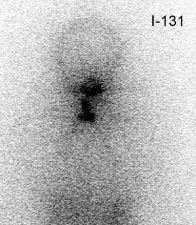

Thyroid Stunning: Diagnostic 2 mCi I-131 scan revealed neck bed activity (oral-pharyngeal, gut, and urinary bladder activity can also be seen). Following treatment with 100 mCi of I-131 the post-therapy scan demonstrated almost no evidence of tracer uptake in the neck indicative of thyroid stunning. Note hepatic activity consistent with breakdown of radiolabeled thyroxine. |